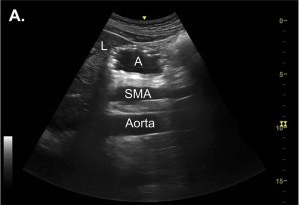

20.2 The structure labelled A shows (gastric ultrasound image shown)

a. Empty stomach

b. Full stomach with Solids

c. Full stomach with liquids and Air

d. Gall Bladder

e. Abdominal Aorta